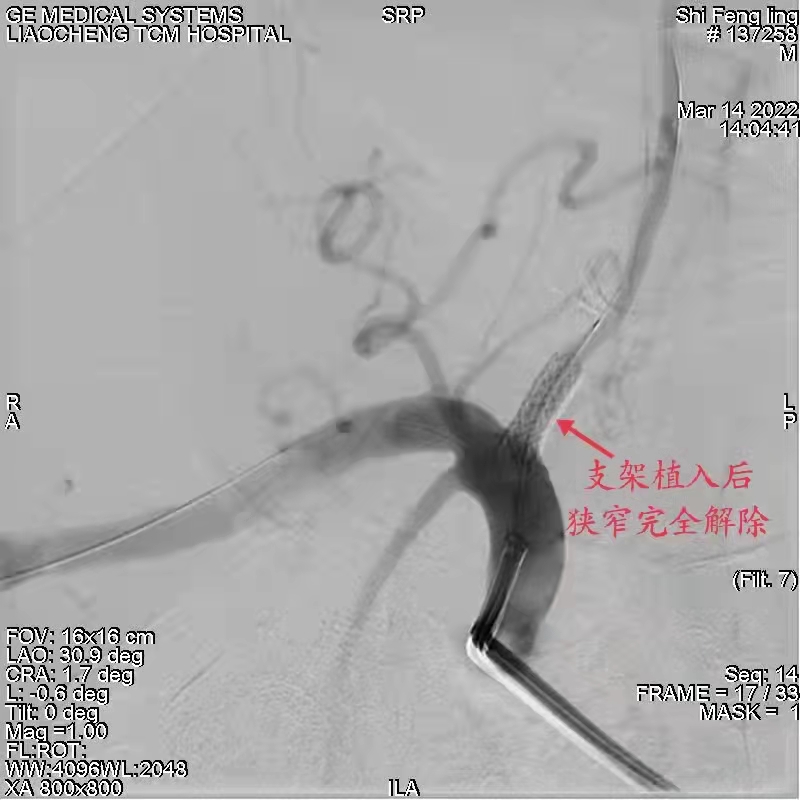

近日,患者石某因头晕数月余来我院治疗,行脑血管造影术示右椎动脉起始部重度狭窄,由我院神经介入团队、北京天坛医院介入中心张义森教授查看病人,近日局麻下行右椎动脉起始部重度狭窄支架植入术,支架植入后,狭窄完全解除,右椎动脉各段显影良好,患者后循环缺血症状明显改善。

术后